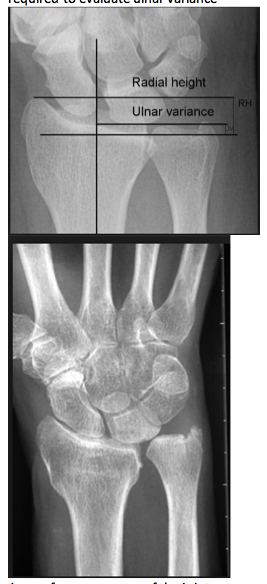

How is the load distribution in the wrist affected by ulnar variance?

What conditions are associated with the pathological finding of this XR?

Ulnar Negative Variance

How does position of the forearm affect ulnar variance?

A pronated grip view is the best to determine your ulnar varience

Pathophysiology of altered ulnar variance